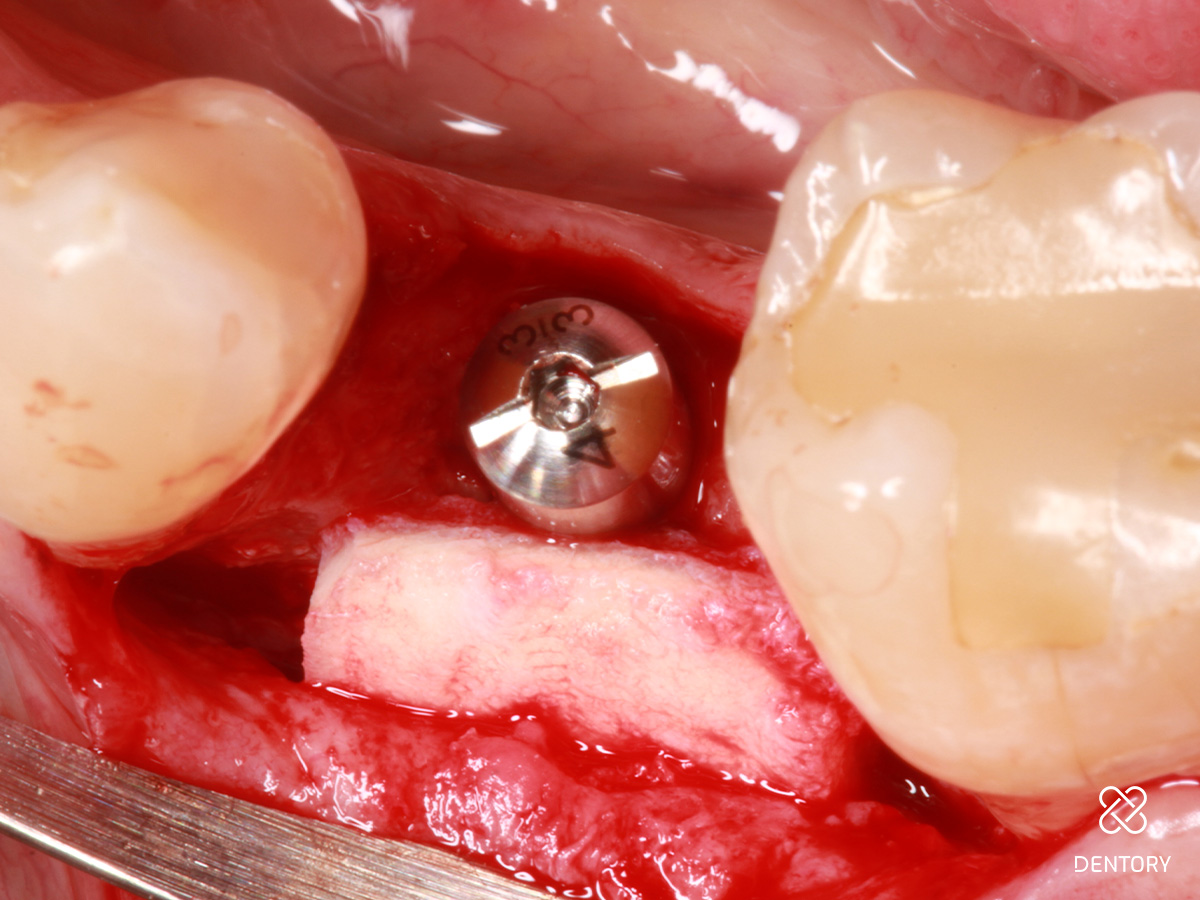

Abbildung 3

Okklusale Ansicht nach Insertion eines 4 mm-Implantats mit Plattform-Switching. Eine simultane Defektrekonstruktion erscheint möglich.